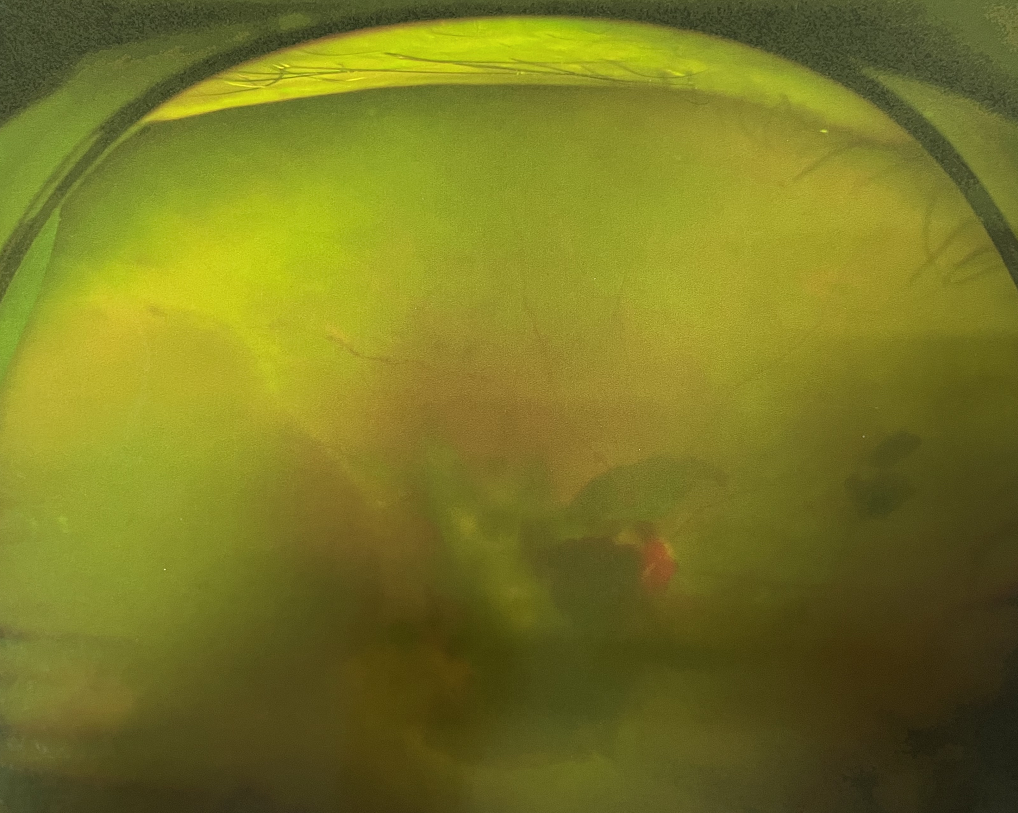

糖尿病視網(wǎng)膜病變能治愈嗎?

【文章導(dǎo)讀】糖尿病視網(wǎng)膜病變是糖尿病在眼部的主要并發(fā)癥,是我國(guó)四大致盲眼病之一,主要以視網(wǎng)膜血管改變?yōu)椴±硖卣鳌Q鄣锥啾憩F(xiàn)為視網(wǎng)膜出血、滲出、新生血管及增殖膜形成,嚴(yán)重威脅患者

糖尿病視網(wǎng)膜病變是糖尿病在眼部的主要并發(fā)癥,是我國(guó)四大致盲眼病之一,主要以視網(wǎng)膜血管改變?yōu)椴±硖卣鳌Q鄣锥啾憩F(xiàn)為視網(wǎng)膜出血、滲出、新生血管及增殖膜形成,嚴(yán)重威脅患者的視覺健康。

糖尿病視網(wǎng)膜病變患者早期可能沒有明顯的視力下降,有些患者因?yàn)椴Aw出血會(huì)出現(xiàn)突然視力下降,晚期患者視力多有明顯下降。

糖尿病視網(wǎng)膜病變

糖尿病視網(wǎng)膜病變可分為六期:

?、衿冢河形⒀芰龌虿⒂行〕鲅c(diǎn)。

?、蚱冢河悬S白色“硬性滲出”或并有出血斑。

?、笃冢河邪咨?ldquo;軟性滲出”或并有出血斑。

?、羝冢貉鄣子行律芑虿⒂胁Aw積血。

?、跗冢貉鄣子行律芑虿⒂欣w維膜增生。

?、銎冢貉鄣子行律芑虿⒂欣w維膜增生,并發(fā)視網(wǎng)膜脫離。